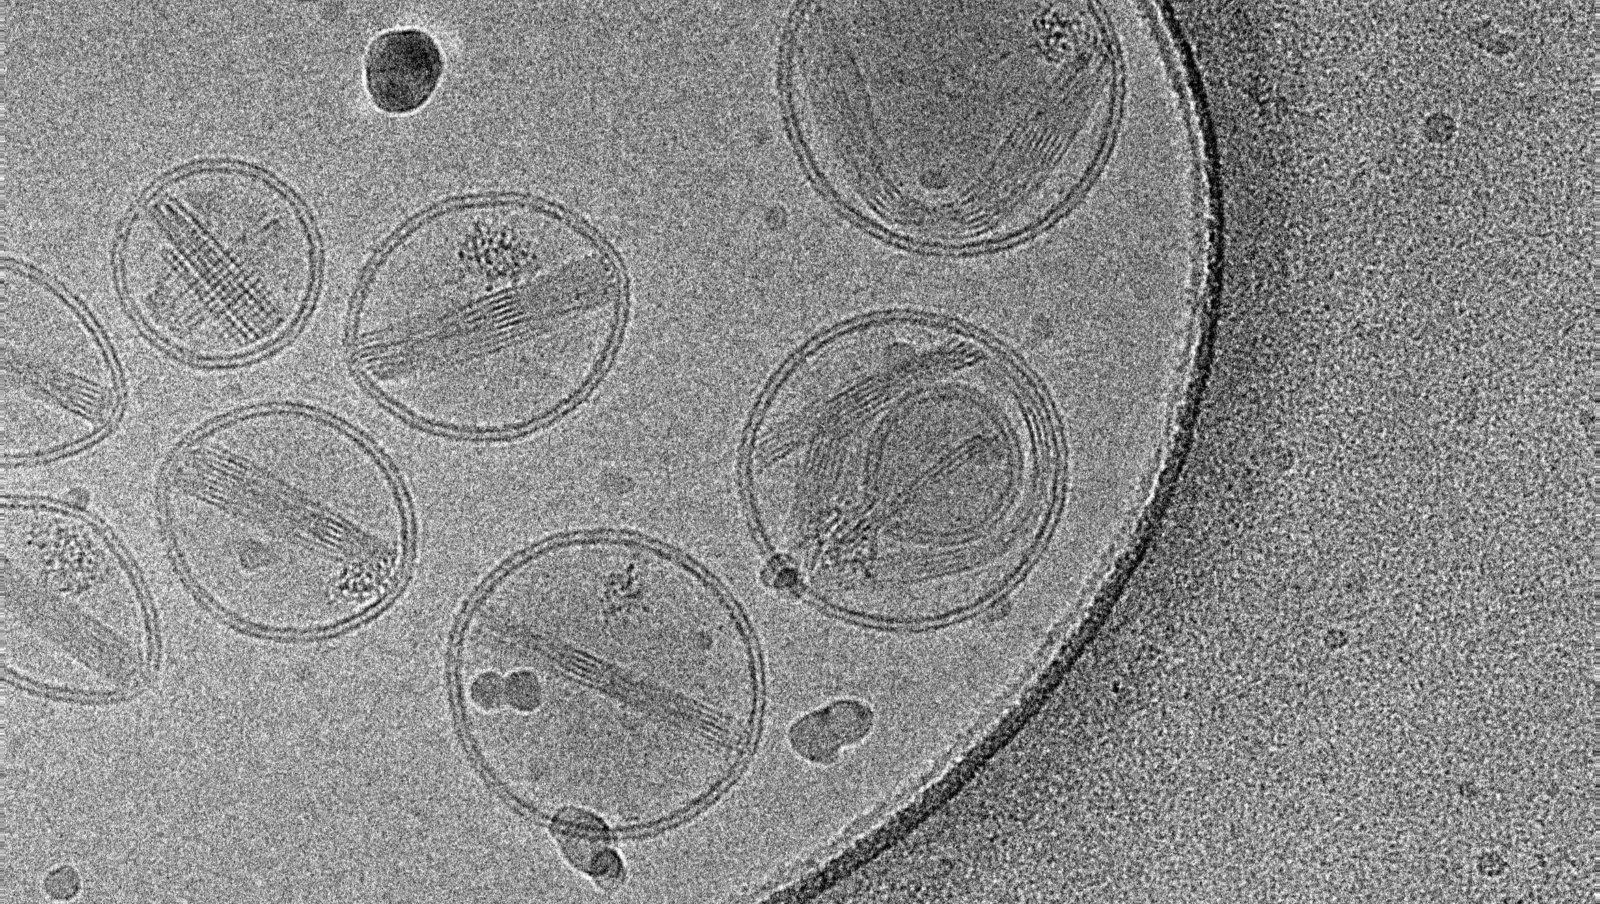

Jak pokazują ostatnie doniesienia, nanocząsteczki, które są coraz powszechniej stosowane w różnych dziedzinach, mogą należeć do czynników toksycznie działających na makrofagi. Jest to szczególnie istotne spostrzeżenie z uwagi na fakt, że to właśnie te komórki odpornościowe często jako pierwsze napotykają nanocząstki w organizmie człowieka. W ostatnich badaniach wykazano toksyczność in vitro większości nanocząstek, co zwiększyło pilną potrzebę zajęcia się profilami ich bezpieczeństwa.